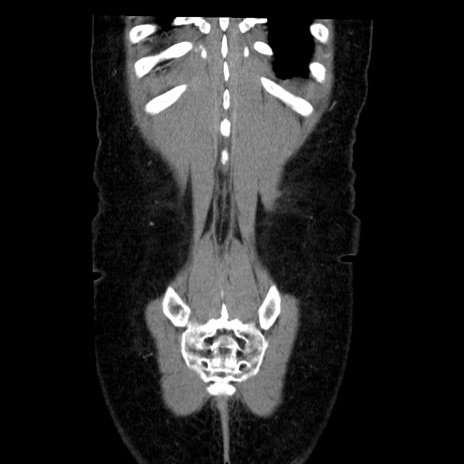

矢状断像